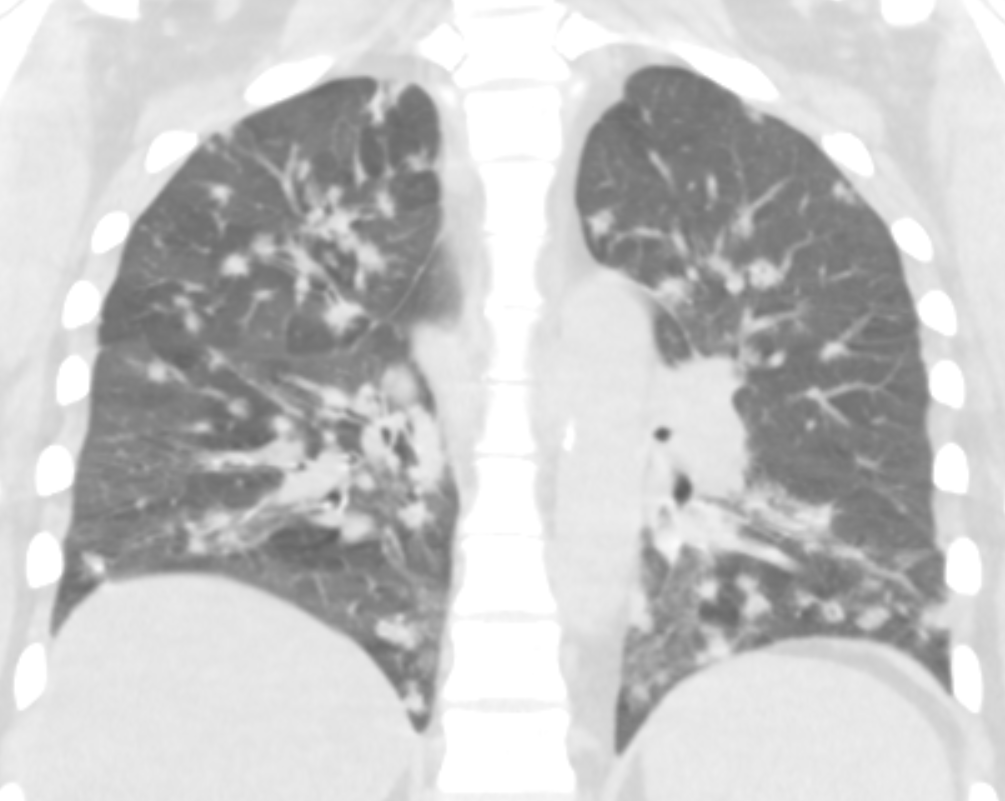

@jonherochung I find that patients with this distribution of airway-predominant disease due to sarcoidosis are the ones who become very exercise limited in longitudinal follow up - and harder to treat. Clinically can be very different vs. upper lobe distributive sarc. Great image Jonathan!

A reminder that sarcoidosis can primarily affect the airways. In this case, there is florid air-trapping and peribronchial nodules and bronchial wall thickening.